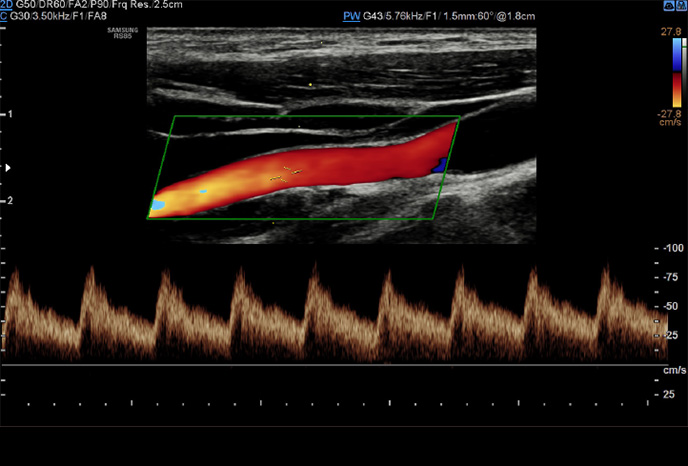

Arterial Analysis™

Nástroj pro detekci funkčních změn kardiovaskulárních cév

Arterial Analysis ™ detekuje funkční změny cév a poskytuje naměřené hodnoty, jako je tuhost, tloušťka intima-média a rychlost pulzní vlny karotidy. Protože funkční změny nastávají před morfologickými změnami, podporuje tato technologie včasné odhalení kardiovaskulárních onemocnění.